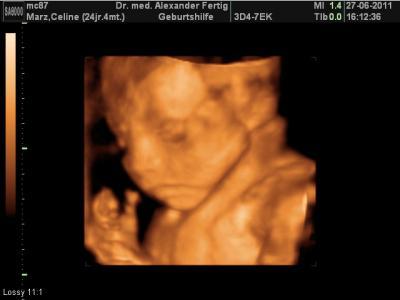

Hallöchen meine runden Kugeln , hatte heute wieder einen Termin bei meinem Gyn. alles supi...Baby hat kräftig zugenommen! Wiegt nun 625g, liegt genau im Normalbereich, lt. meines Arztes. Ach wie süss... die kleine Maus musste während der Schallung 2x gähnen . Hat sogar 1x gelächelt sieht man alles auf den Videos, die man hier leider nicht hochladen kann . Ach, ich hab jetzt übrigens auch ne Fledermaus...das darf Sie bis zur Geburt auch gern bleiben. In 3 Wochen lass ich dann den Zuckertest machen.

Das sind ja tolle Neuigkeiten. Dein Baby ist ja seehr süß Ich finde es immer wieder erstaunlich, wie gut man auf diesen Bildern die kleinen Gesichtchen sieht :-) Ich darf morgen wieder hin, und hoffentlich habe ich dann auch so einen tollen Blick. Beim letzten Mal hatte die Kleine Nabelschnur und Hände vorm Gesicht und man konnte gar nichts sehen. Liebe Grüße

danke schön anfangs fand ich 3d etwas unheimlich aber je mehr sie zunimmt desto schöner werden die bilder. lässt du auch 3d ultraschall machen?

ja genau, mein arzt macht immer zuerst "normale" beschallung um nach dem rechten zu sehen wie oberschenkellänge, bauchumfang, kopfumfang...alles was er so wissen möchte und dann schaltet er in den 3d modus, dass ich auch was von der schallung hab :-P ich hab einmalig 60€ gezahlt und bekomm alle bilder und videos auf ne cd jedesmal gebrannt.